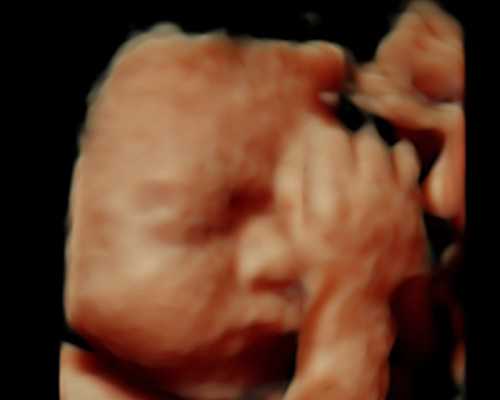

着床是指受精卵着床,受精卵形成后,会随着输卵管纤毛的摆动以及蠕动,进入到女性的子宫宫腔内,寻找合适的位置进行着床,与女性的子宫壁嵌合,从而获取母体血液当中的营养继续发育形成胚胎。在这整个过程中多数人没有特殊的症状,所以容易被女性忽略。但是对于体质比较敏感或者特殊的人群可能会有一些临床症状,比如浑身酸痛。另外部分人群可能还会有体温增加、小腹疼痛、分泌物增多以及阴道少量出血等症状,这些都属于正常的现象,一般无需治疗。在停经10天左右的时候,就可以到医院进行抽血检查,明确是否妊娠。